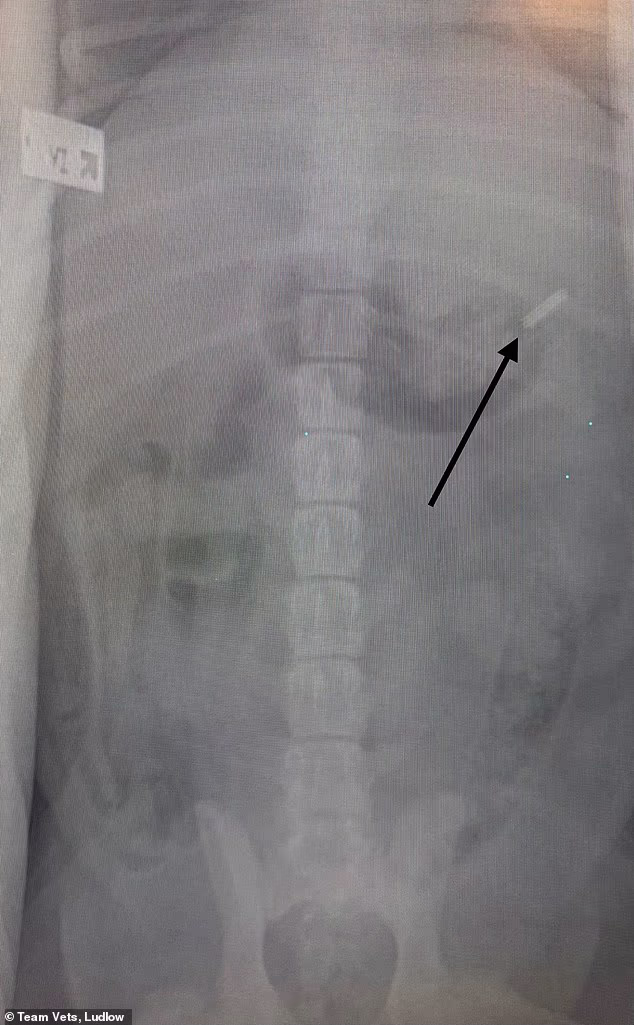

Charlie foi à faca depois que um raio-X revelou uma lâmina de 39 mm presa em seu estômago – e voltou para casa mais tarde no mesmo dia, após uma cirurgia de emergência para remover o objeto.

Um raio-X confirmou que Charlie tinha uma lâmina de 39 mm (1,5 polegada) em seu estômago

‘Os raios X confirmaram as suspeitas dos proprietários, então Charlie foi submetido a uma cirurgia de emergência, pois era a única opção.’